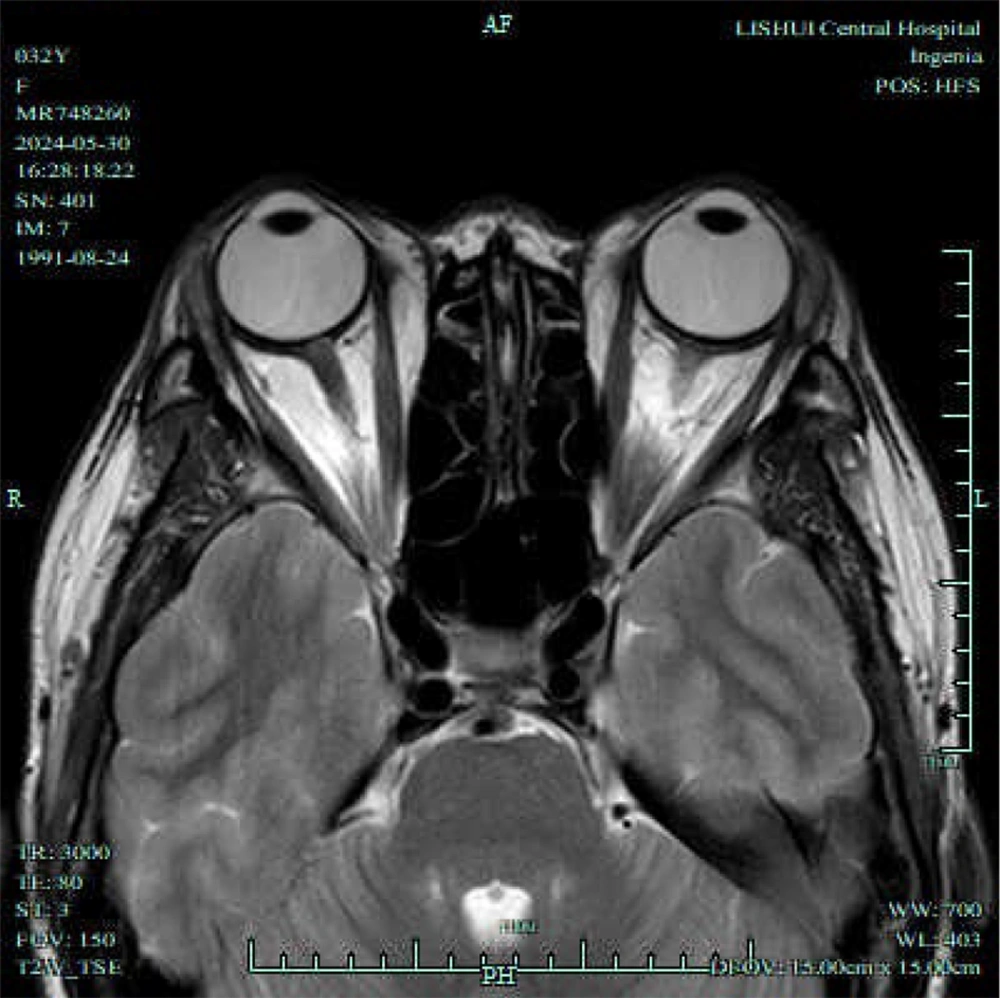

To evaluate the feasibility of Dixon and T2 localization for assessing disease severity and progression, this study examined the measurement parameters of both active and inactive groups, as illustrated in Figures 2 and 3. Tables 3 and 4 present the results. The active group demonstrated significantly higher average EOM water fraction (0.98 ± 0.25 vs. 0.80 ± 0.16), average EOM water signal intensity (398.96 ± 102.45 vs. 326.70 ± 80.46), average EOM fat signal intensity (96.32 ± 12.15 vs. 78.90 ± 10.48), average lacrimal gland signal intensity (79.52 ± 10.24 vs. 68.60 ± 10.12), average of unilateral four EOM fat fractions (67.20 ± 8.82 vs. 50.45 ± 7.60), average EOM T2 value (79.45 ± 7.42 vs. 75.60 ± 6.80), and average EOM cross-sectional area (50.48 ± 7.22 vs. 39.60 ± 6.40) compared to the inactive group. These differences were statistically significant (t = 3.883, 3.469, 6.715, 4.616, 8.899, 2.349, 6.952, P < 0.05).

T1/T2-weighted magnetic resonance imaging (MRI) of an active phase patient. A, Axial T1-weighted MRI shows the most distinct visualization of the enlarged extraocular muscles (EOMs) during the active phase; B, Axial T2-weighted MRI highlights the same EOMs; C, Coronal T2-weighted MRI shows the most distinct visualization of the enlarged EOMs during the progression phase; D, Sagittal T2-weighted MRI highlights the same EOMs.